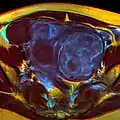

Diagnosis

Physical examination and ultrasound are sufficient for diagnosing uterine fibroids in the majority of patients. When ultrasound findings are inconclusive, magnetic resonance imaging (MRI) may be able to confirm the diagnosis of uterine fibroids in most cases. In addition, MRI can identify benign uterine fibroids with atypical imaging features and fibroids with variant growth patterns. MRI can also identify other uterine (e.g. adenomyosis, endometrial polyps, endometrial cancer) and extrauterine (e.g. benign and malignant ovarian tumors, endometriosis) disorders that may mimic the appearance of uterine fibroids and/or contribute to the patient's symptoms.[37] However, a small proportion of uterine fibroids can mimic other malignant uterine tumors (e.g. leiomyosarcoma) on all available imaging modalities (e.g. ultrasound, CT, MRI and PET-CT).[37]

Malignant tumors of the uterine wall (e.g. leiomyosarcoma) are very rare. Findings suggestive of a malignant uterine tumor rather than a benign fibroid include, fast or unexpected growth (particularly after menopause), interruption/effacement of the endometrial stripe, lymph node enlargement, invasion of adjacent organs and metastases to distant organs (e.g. lung). MRI findings suggestive of a malignancy include nodular/ill-circumscribed tumor margins, intermediate/high T2-weighted signal intensity of the solid tumor components, regions with high signal T1-weighted sequences in keeping with subacute hemorrhage, fine/wispy enhancement of the solid parts of the tumor, and restricted diffusion on diffusion-weighted imaging (DWI).[37] A biopsy is rarely performed and if performed, is rarely diagnostic. Should there be an uncertain diagnosis after ultrasounds and MRI imaging, surgery is generally indicated.[38]